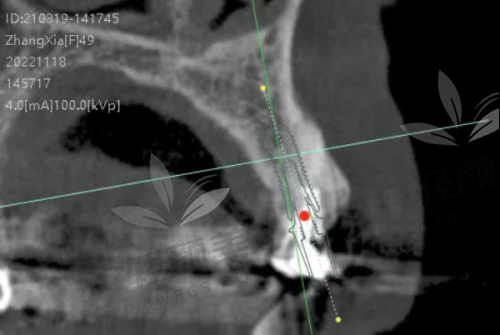

我按照预约的时间来到了重庆团圆口腔,医院的环境特别干净整洁,工作人员也都特别热情,一进门就有人引导我去挂号、填资料。见到李志锋医生后,他特别和蔼可亲,详细地询问了我的牙齿情况和病史,还耐心地听我倾诉了牙齿缺失以来的烦恼。然后他给我做了全方面的口腔检查,包括拍X光片和CT,通过这些检查,李医生精细地了解了我牙槽骨的情况。之后,他根据我的检查结果,给我制定了详细的种植牙方案。他给我推荐了以色列种植牙,说这种种植牙的材质和性能都特别好,而且价格也比较实惠,3500起就能做,性价比非常高。他还跟我解释了整个种植过程和术后的注意事项,让我心里有了底。